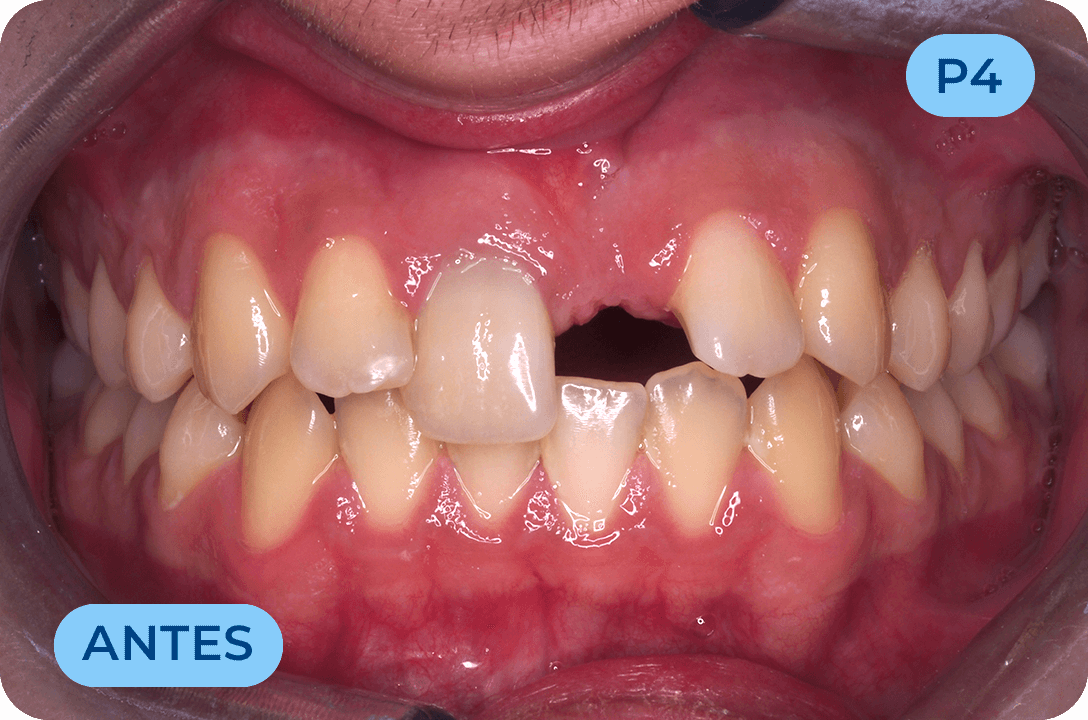

Ortodontia

É a especialidade da Medicina Dentária que se debruça sobre o estudo e correção das más posições dentárias e dos maxilares. Atualmente é possível tratar pacientes de todas as idades, no entanto a 1ª consulta deve ser realizada ainda na infância para intercetar eventuais problemas de desenvolvimento esquelético e funcional.